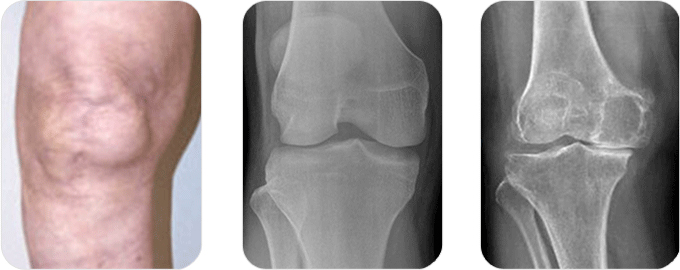

관절 내시경은 흔한 수술 방법으로 작은 카메라를 삽입하여 관절을 관찰하는 방법입니다. 관절 내시경은 무릎 관절 내부의 영상으로 무릎 안의 문제를 진단 및 치료하는데 도움을 줍니다. 기술적으로는 고해상도 모니터, 카메라를 이용하여 무릎 문제를 치료하는데 가장 효과적인 수술 기구입니다.

관절 내시경은 작은 절개를 통해 시행되게 되며 이 삽입구를 통해 작은 카메라가 달려있는 관절 내시경을 관절 안으로 삽입하게 되며 이 카메라에서 영상을 모니터로 전송하게 되고 이 모니터를 통해 보다 자세히 관찰할 수 있습니다. 손상된 조직을 제거 혹은 봉합하기 위해선 작은 수술도구가 필요하게 되며 이들 도구는 무릎의 반대편에 작은 절개를 통한 삽입구로 삽입되어 사용되게 됩니다.

수술 방법

무릎에 몇 개의 작은 삽입구를 형성하게 되고 소독된 물을 무릎 관절 안으로 주입합니다. 무릎을 부드럽게 하고 시야를 깨끗이 확보하여 더 선명한 영상을 얻을 수 있습니다.

가장 중요한 목적은 관절 내시경을 이용하여 정확한 진단을 하는 것이며 만약 수술적 치료가 필요한 경우 수술 도구를 직접 삽입하여 치료를 동시에 시행할 수 있습니다. 검사 진행은 약 10분 정도의 시간이 소요되며 필요한 수술 시간은 관절 내시경을 통해 보이는 손상 정도나 치료 방법에 따라 달라지게 됩니다.